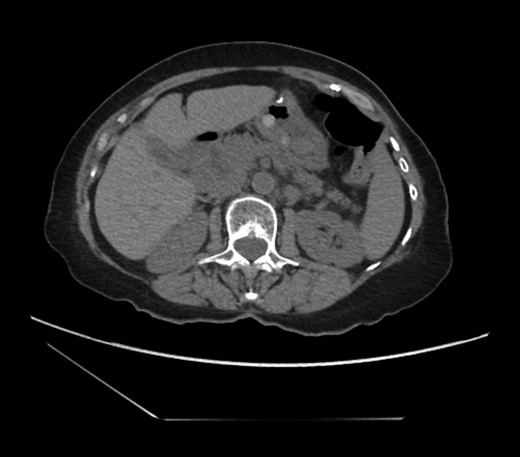

An 81-year-old female with a medical history of CAD with stents, hyperlipidemia, hypothyroidism, GERD, recent UTI, pancreatic cyst, constipation, anemia and leukopenia presented to the ED with a 1 day history of mild, diffuse and cramping abdominal pain. The patient was unable to give an accurate history, but the son at bedside supplemented this reporting that for several years the patient had been experiencing ill-defined abdominal discomfort. Physical exam showed a soft abdomen with mild tenderness and no evidence of peritonitis. A CT scan of the abdomen and pelvis with IV and PO contrast (Fig. 1) showed edematous changes to the mesentery of the small and large bowel with swirling of vessels indicative of internal hernia. The stomach was also noted to be distended with both air and fluid as a consequence of posterior compression by the hernia contents (Fig. 2). A surgical consult was obtained, a nasogastric tube and Foley catheter were placed, antibiotics were started, and the patient was taken for an exploratory laparotomy. Upon entering the abdomen through a vertical midline incision, 1.5 l of ascites was drained revealing a diffusely edematous mesentery. A large portion of the small bowel was seen to be herniated through the Foramen of Winslow (Fig. 3). A Kocher maneuver and division of the gastrocolic ligament were then performed to allow release of the herniated small bowel. It was at this time that, in addition to small bowel, a large portion of the ascending and transverse colon was noted to be herniated through the foramen of Winslow. The small bowel was also seen to be torsed about its own mesentery. Normal anatomy was restored and the bowel noted to be healthy and viable with peristalsis (Fig. 4). Due to the large size of the foramen after reduction and enlargement, it was deemed best to leave it open to prevent any further incarceration or strangulation. The abdomen was closed and the patient tolerated the procedure well. At a follow-up visit 2 months later, the patient had well-healed incisions, was doing well, tolerating a diet, and gaining weight appropriately.

Diagnosing an internal hernia is frequently accomplished using physical exam and CT imaging. Abdominal X-ray does have some nonspecific findings suggestive of internal hernia but is usually inadequate for diagnosis. Diagnosis of a foramen of Winslow hernia, however, is only accomplished in 10% of patients preoperatively [3]. As previously mentioned this diagnosis is rare and often presents with vague obstructive type symptoms. This likely contributes to the low occurrence of accurate preoperative diagnosis. However, several radiographic findings were seen in this patient that suggested a foramen of Winslow hernia preoperatively. First, there is visible swirling of the mesentery on the CT scan that is indicative of internal hernia (Fig. 1). Second, there are loops of small bowel that can be visualized between the IVC and the edge of the liver in a supra renal position along the lesser curvature of the stomach (Figs 1 and 2). When compared to a CT of the abdomen and pelvis obtained 4 years prior to presentation, there is actually evidence that this patient had a non-obstructing foramen of Winslow hernia at that time as demonstrated by bowel being visualized in the lesser sack (Fig. 5). These findings, especially small bowel along the lesser curvature of the stomach, are inconsistent with normal anatomy and strongly indicative a foramen of Winslow hernia.

CT abdomen and pelvis coronal view of foramen of Winslow hernia.